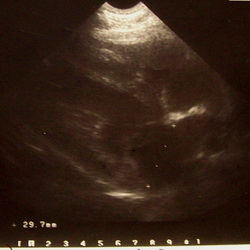

Ultraschalluntersuchungen